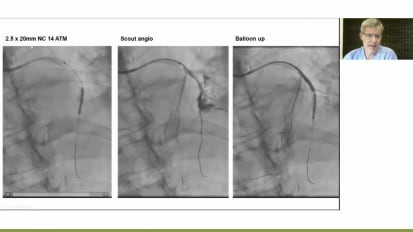

Lifelines for Your Practice: Case-Based Approaches to Perforation Management

A coronary artery perforation is one of the most feared complications in PCI. Drs. Kevin Croce, Duane Pinto and Jason Wollmuth discuss advanced perforation management techniques.